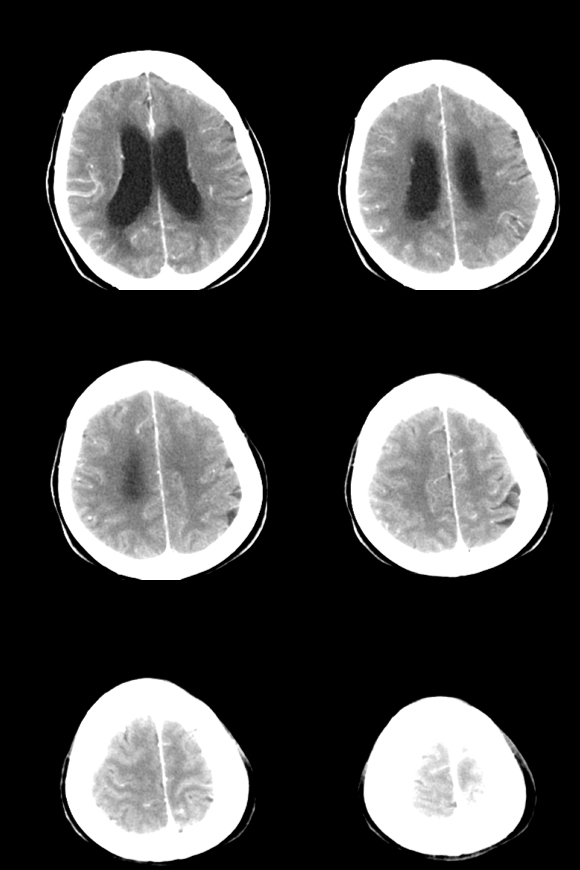

标题: CT18179:F67y,反复头昏、头痛。 [打印本页]

标题: CT18179:F67y,反复头昏、头痛。

67岁女性,头昏、头痛1年+。

小脑蚓部血管母细胞瘤伴脑室扩张积水。

支持考虑:小脑蚓部血管母细胞瘤伴梗阻性脑积水。

病人子女考虑患者年龄已较大,选择行脑室-腹腔分流术,失访,太遗憾了。